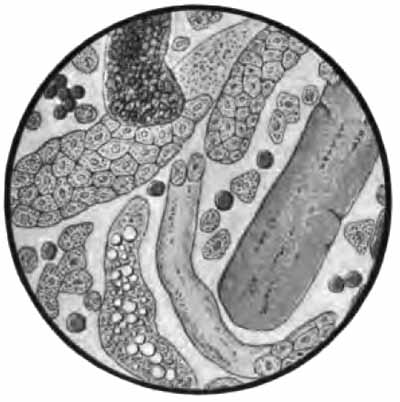

Sputum from a case of asthma

FIG. 13.—Different morphologic elements of the sputum (unstained): a, b, c, Pulmonary or alveolar epithelium—a, with normal lung pigment (carbon); b, with fat-droplets; c, with myelin globules; d, pus-corpuscles; e, red blood-corpuscles; f, cylindric beaker-shaped bronchial cells; g, free myelin globules; h, ciliated epithelium of different kinds from the nose, altered by coryza; i, squamous cells from the pharynx (after Bizzozero).

(b) Cylindric cells from the nose, trachea, and bronchi (Fig. 13, f, h): These are not usually abundant, and, [p. 43] as a rule, they are not identified because much altered from their original form, being often spheric.

(c) Alveolar cells: rather large, round, or oval cells with one or two round nuclei (Fig. 13). Their source is presumably the pulmonary alveoli. Like the leukocytes, they frequently contain particles of carbon (normal lung pigment). In chronic heart disease, owing to long-continued passive congestion, they may be filled with brown granules of altered blood-pigment, and are then called "heart-failure cells" (Plate II, Fig. 1). Alveolar cells commonly contain fat-droplets and, less frequently, myelin globules. The latter are colorless, rounded bodies, sometimes resembling fat droplets, but often showing concentric or irregularly spiral markings (Fig. 13, c, g). They are also found free in the sputum. They are abundant in the scanty morning sputum of apparently healthy persons, but may be present in any mucoid sputum.